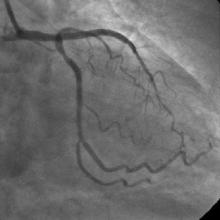

The left system was engaged with XB 3.5 guiding catheter through the femoral route. With the help of a 1.1x1.5mm CTO balloon, we directed a Shinobi guidewire towards the ostial LAD lesion (Figure 4). After making sure that the guidewire was pointing towards the CTO with its tip at the CTO lesion, we used the torquer to gently twirl the guidewire without forcing or overly manipulating it and allowed the guidewire to find its own way through the CTO by patiently twirling it at the lesion site. Within a few minutes, the guidewire jumped through the CTO lesion (Figure 5) and then through the lesion with the help of the CTO balloon (Figure 6). The path was first confirmed by engaging the RCA from the radial approach and injecting dye into the RCA (Figure 7). The CTO was then predilated with a 2.0x30mm Sapphire balloon (Figure 8 and Figure 9) and stented it with a 3.0x36mm DES (Figure 10 and Figure 11). Later the RCA was engaged with a JR 3.5 guiding catheter. A Cougar guidewire crossed the RCA lesion that was directly stented with a 3.0x13mm BMS (Figure 12 and Figure 13).

No residual stenosis found, TIMI III flow achieved distal to the lesion.